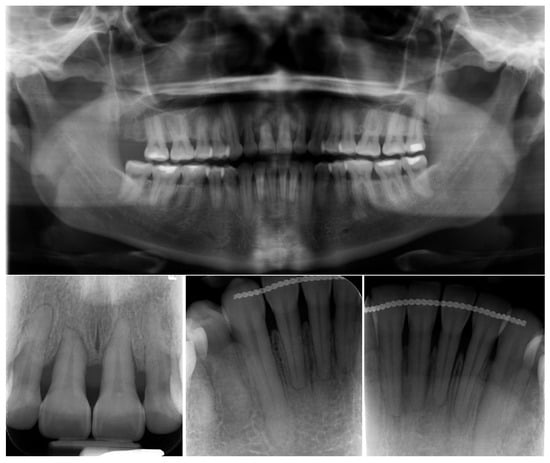

2. Case Presentation

2.1. Diagnosis and Etiology